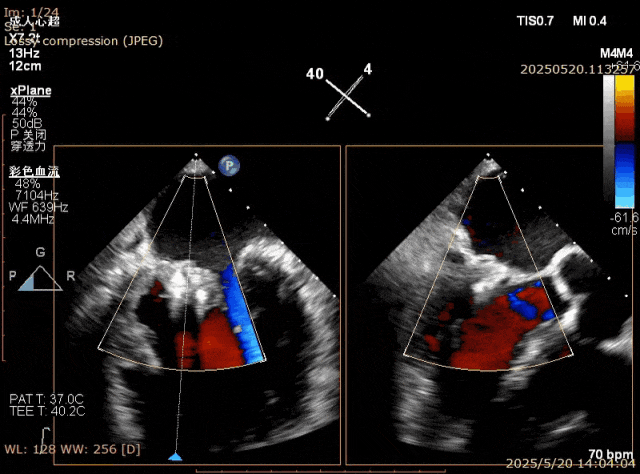

在经股静脉途径的TEER手术时,房间隔穿刺是一个很重要的基础步骤。有时候房间隔组织较韧较厚(多见于房间隔短穿刺位置需要靠后,或者外科房间隔修补术后),穿刺针通过之后要通过导引大鞘(GC)存在着较大困难,若强行推送大鞘可引起房间隔撕裂到左心房顶引起灾难性心包填塞。传统做法时使用外周球囊对房间隔进行扩张,但是不是每个导管室都常规配备外周球囊,且使用过大球囊仍可引起房间隔撕裂风险。我们提供了一种更简洁的方式,即使用导引鞘内芯和房间隔穿刺鞘两个管子(双管齐下)同时扩张房间隔穿刺口,再推送导引大鞘通过房间隔,无需额外器械,操作简单高效且安全(图1-4)。

图1. 房间隔穿刺处肥厚,GC难以通过房间隔